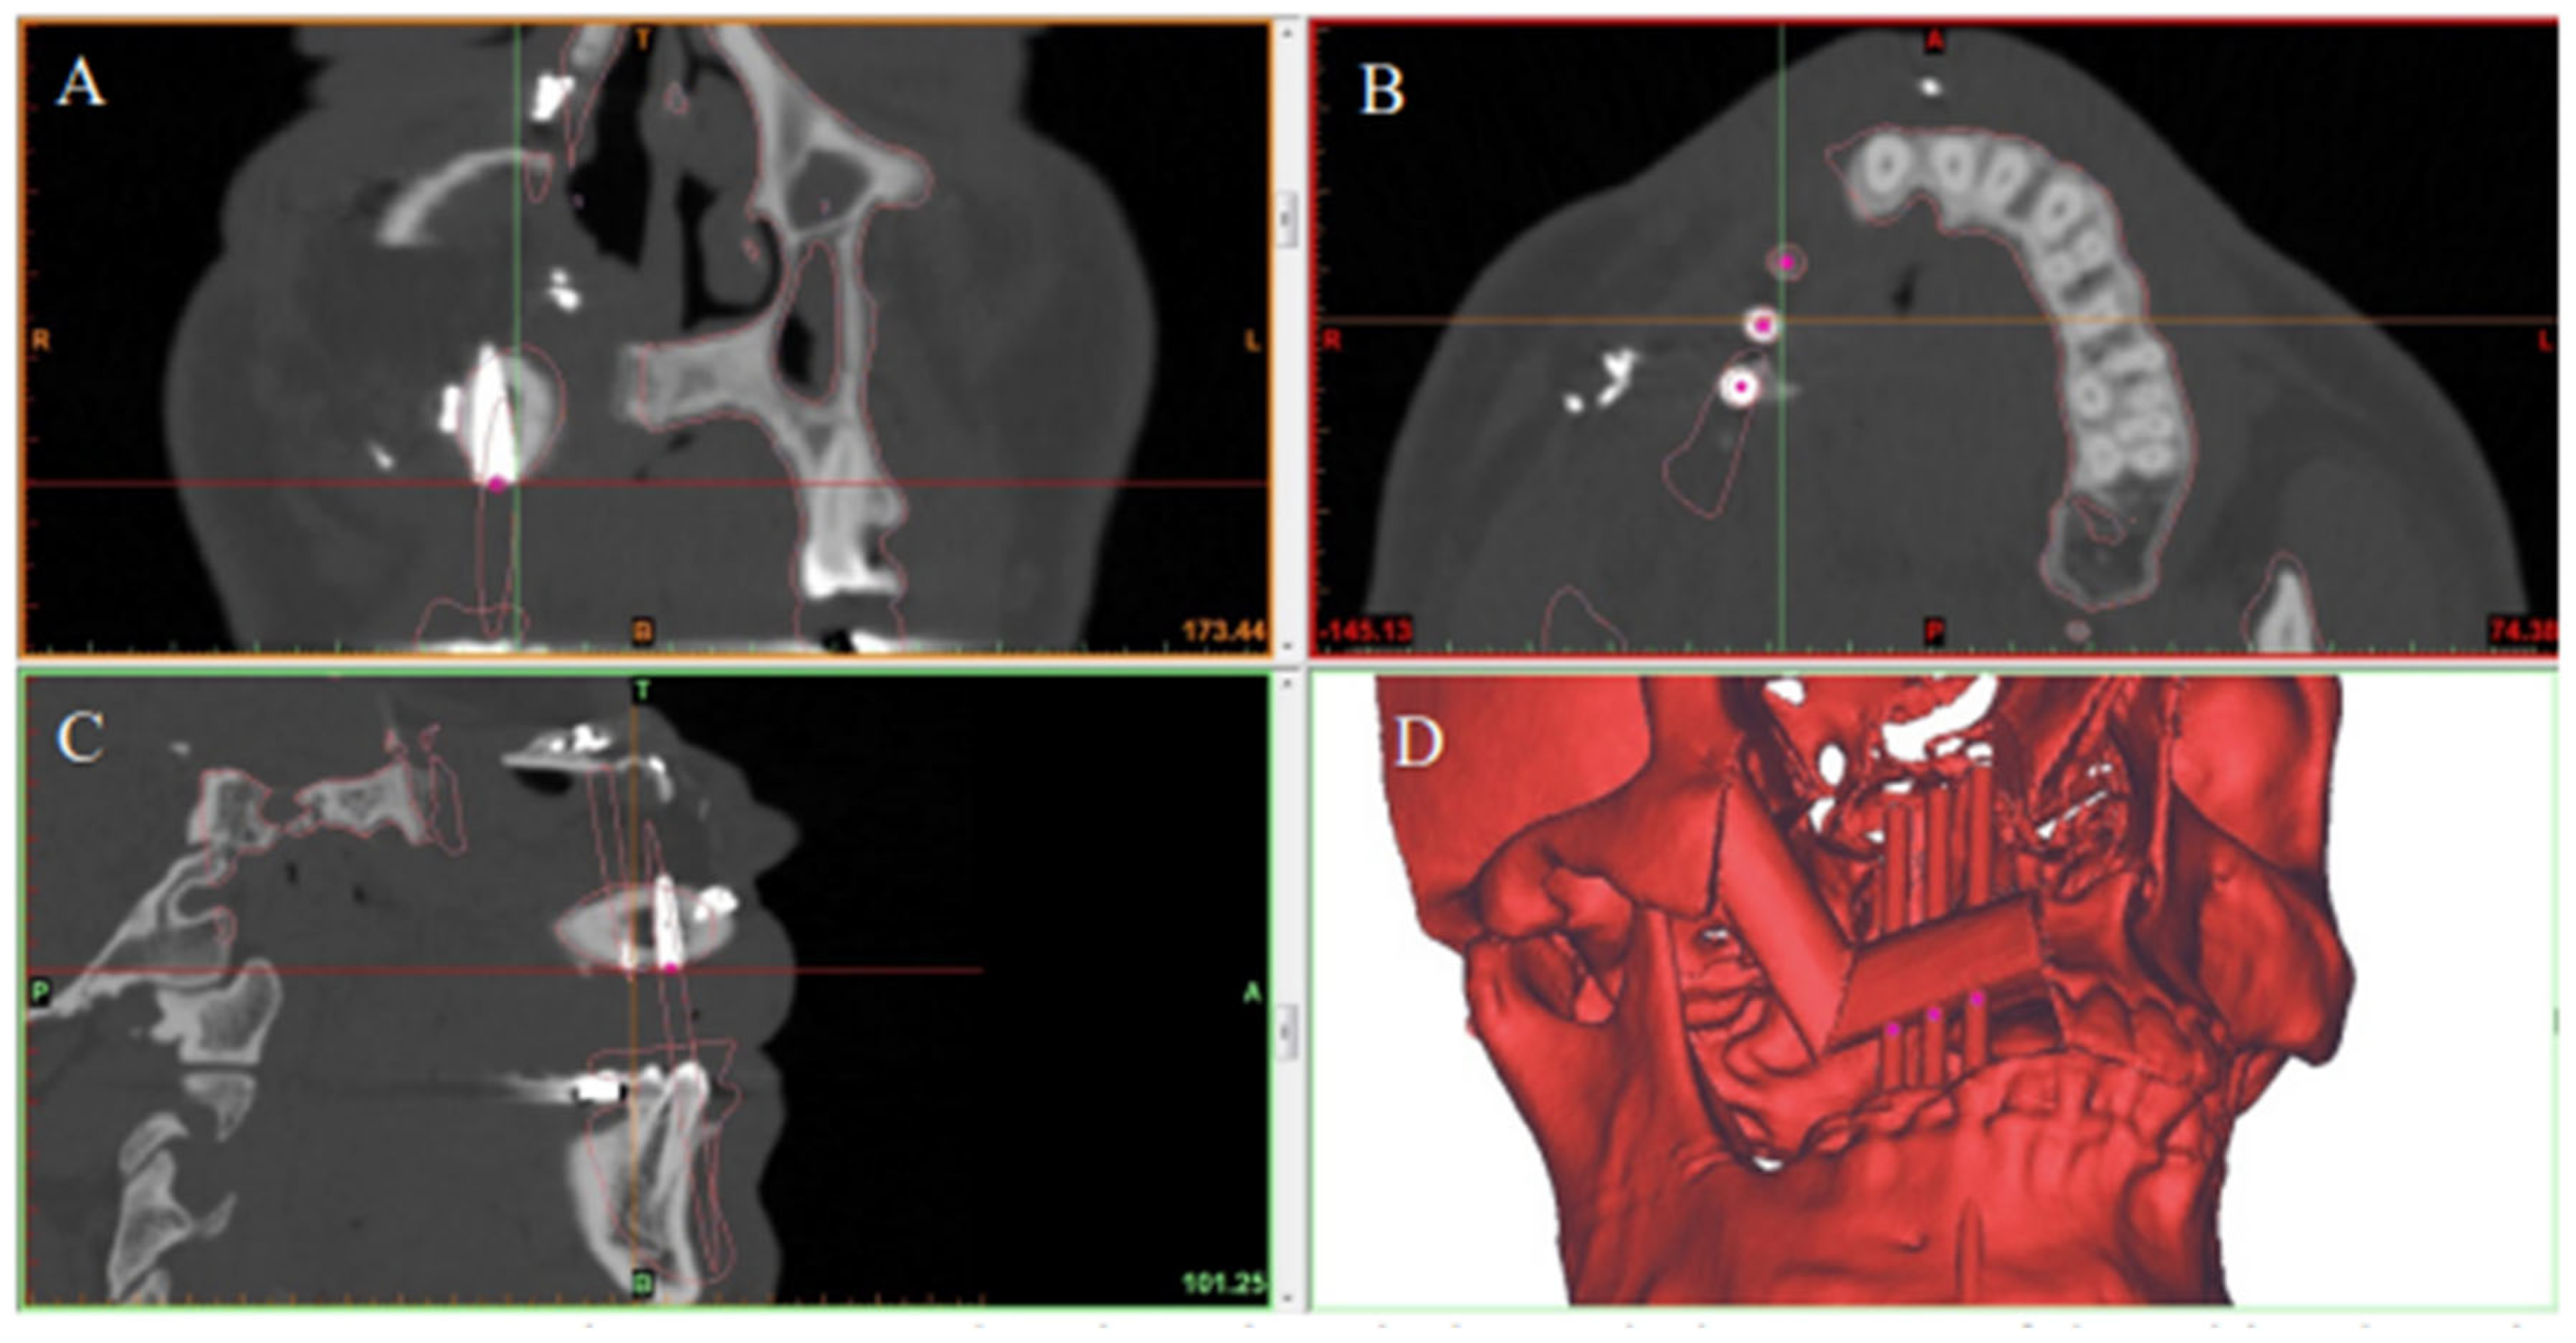

The primary outcome of this study was the accuracy of the postoperative implant positions as compared to the SDS plan. Each patient had a high-resolution helical CT scan of the facial bones using either a Somatom Sensation (Siemens, Germany) or a GE VCT (GE Healthcare, Waukesha, WI) 64-slice CT select scanner via a 0.625 mm collimation with a 25.0 cm field of view and 0 degree gantry tilt. All patients had postoperative CT scans of their facial bones 6–12 months after the Stage II procedure.

2.6. Data Analysis

The preoperative digital plan, referred to as “planned”, and the scans of the postoperative results, referred to as “actual”, were used for our analysis. Digitally placed spheres (1 mm diameter) were manually positioned in the geometric center of the planned and actual implant positions along the occlusal surface of the fibula. The spheres defined the reference point for measuring implant position. The X, Y, and Z coordinates of each planned and actual implant position were obtained (Figure 5 and Figure 6). The difference in position of the dental implants between the preoperative planned and postoperative actual CT scans was calculated in millimeters.

When the postoperative scans were superimposed on the preoperative SDS plans, the mean center-point distances between the actual and planned implant positions were 1.5 mm (SD ± 1.2 mm) in the X axis, 2.0 mm (SD ± 1.0 mm) in the Y axis, and 1.8 mm (SD ± 1.1 mm) in the Z axis (Figure 7).

Figure 6. Postoperative CT scan showing the actual position of dental implants in the reconstructed jaw in the (A) coronal, (B) axial, and (C) sagittal planes. (D) 3D model showing final jaw reconstruction with implants in their actual position.